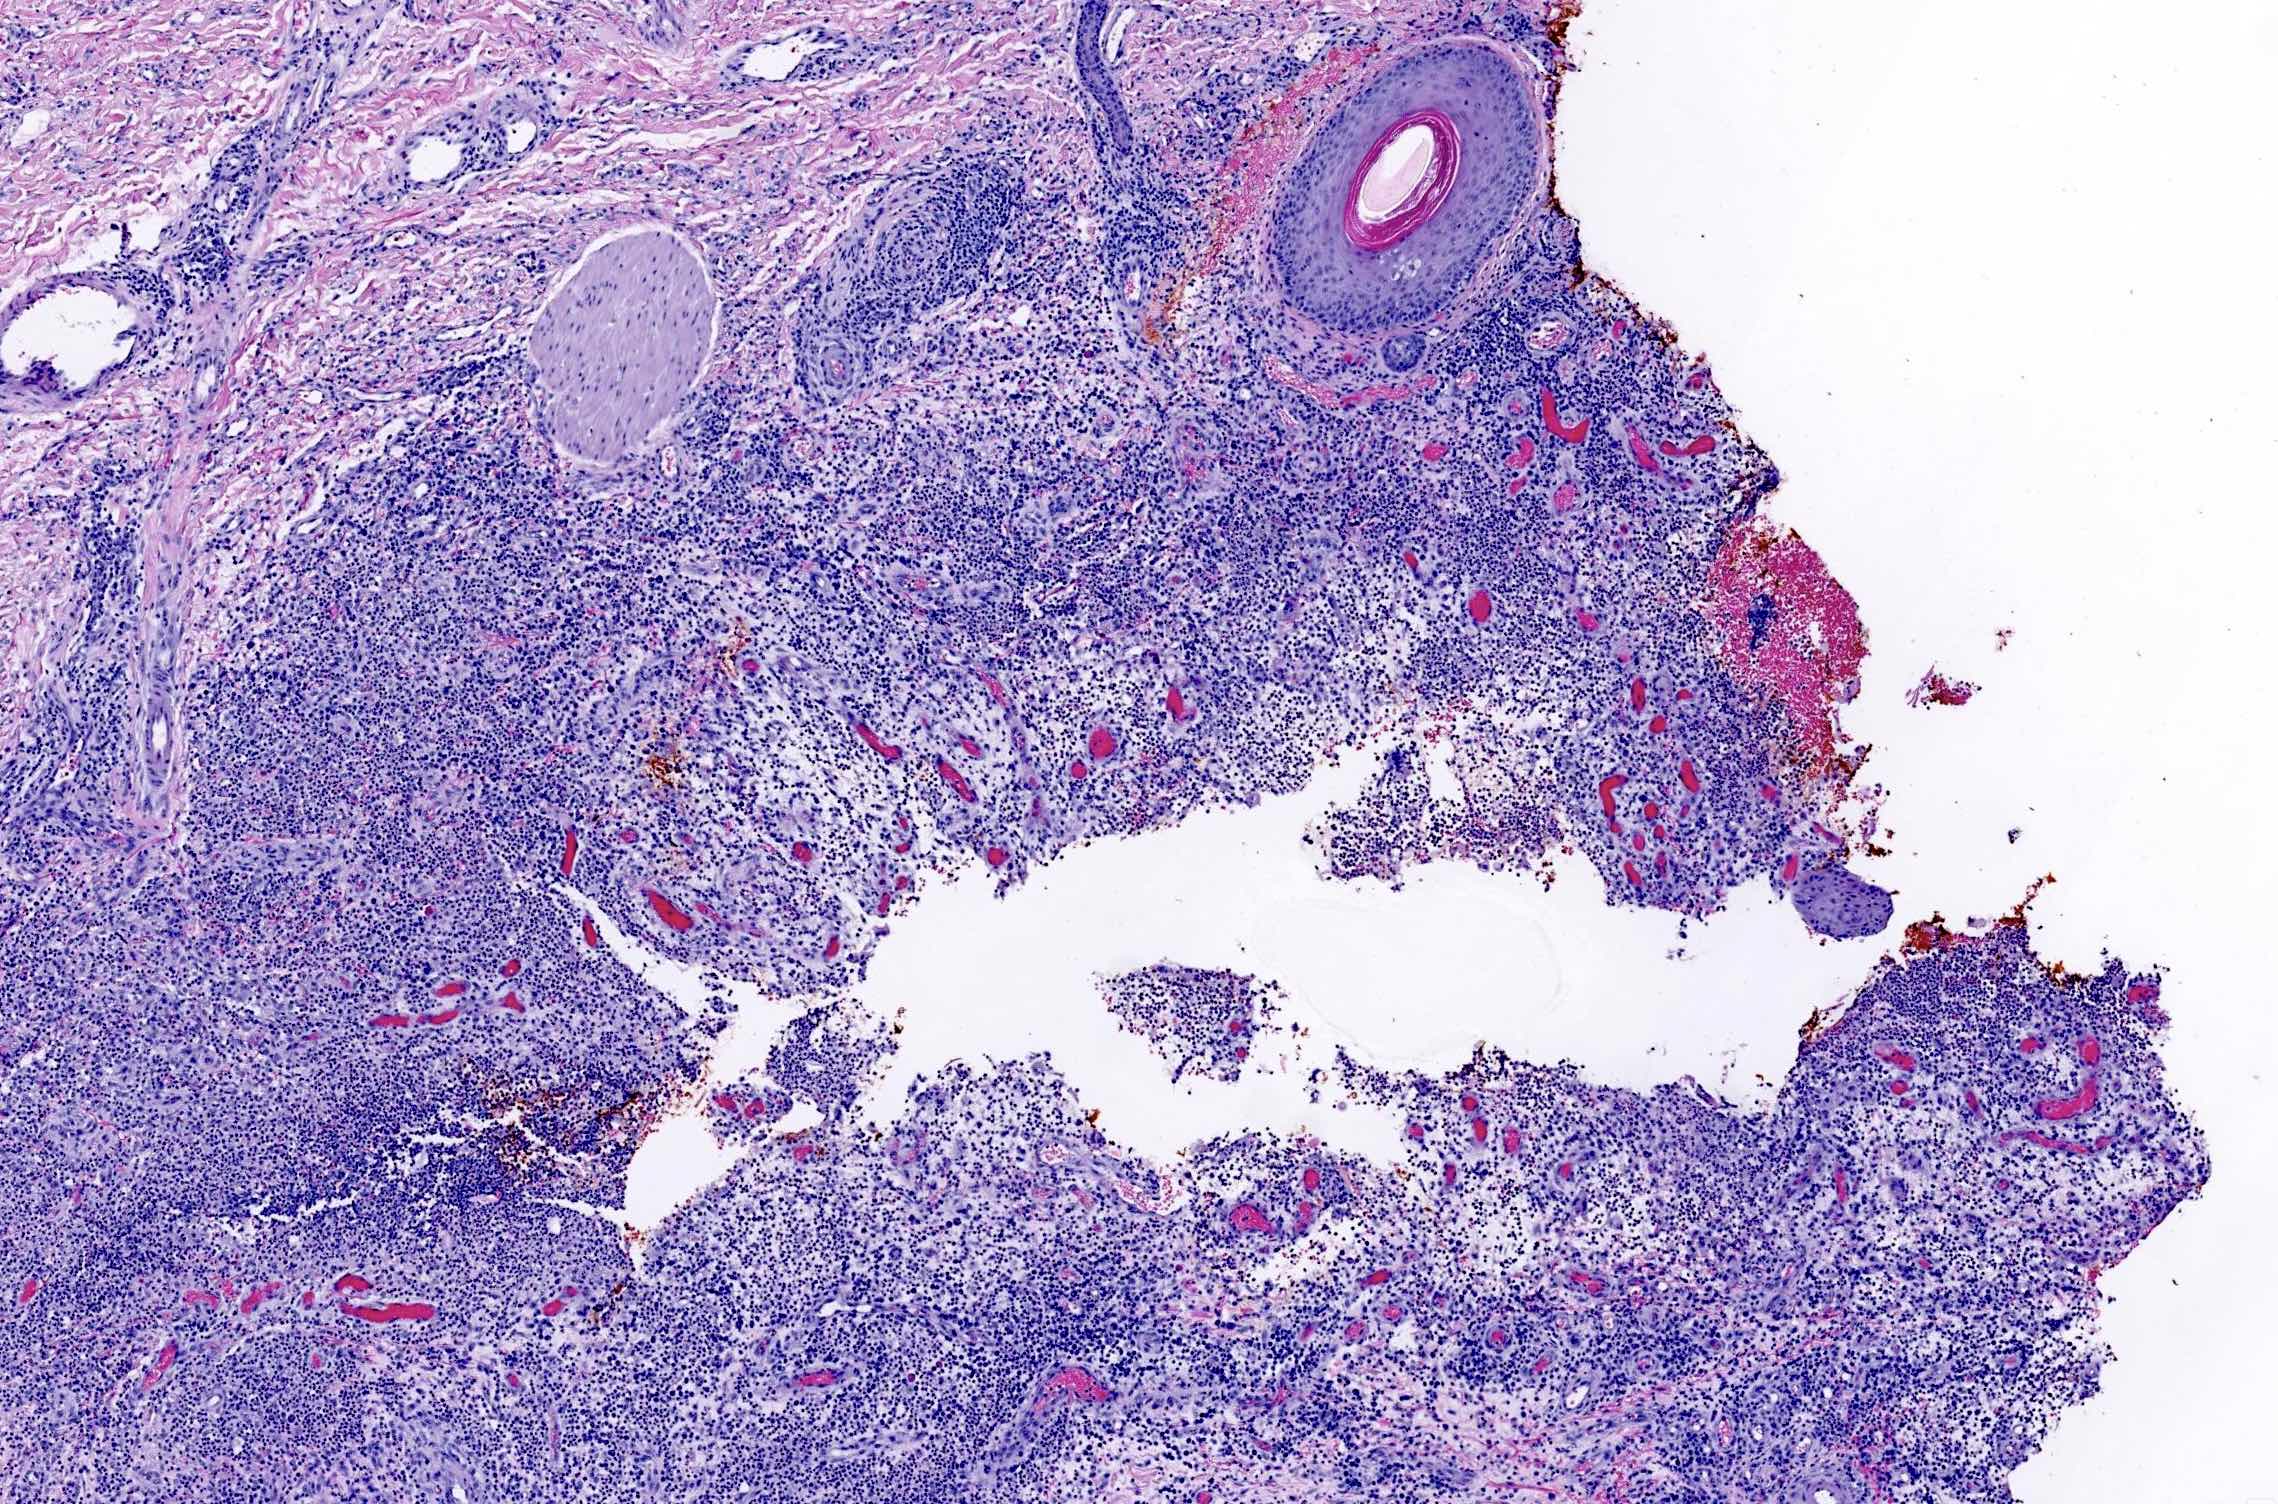

Microscopic (histologic) description

- In early lesions: follicular hyperkeratosis, hyperplasia of follicular epithelium and perifolliculitis (Br J Dermatol 2011;164:367)

- Dermal mixed inflammatory cell infiltrate, sometimes extending into the subcutis (Br J Dermatol 1990;122:763)

- Neutrophilic abscesses, which may connect with squamous epithelium lined cysts and sinus tracts that extend to the skin surface (Br J Dermatol 1990;122:763)

- Cysts and sinus tracts contain laminated keratin and occasional hair follicles (Br J Dermatol 1990;122:763)

- Granulation tissue with occasional foreign body giant cells present in ~25% of cases (Histopathology 1993;23:111)

- Inflammation involves apocrine glands in a minority of cases (J Am Acad Dermatol 1996;34:994)

- Dense fibrosis surrounding areas of follicular rupture

Microscopic (histologic) images